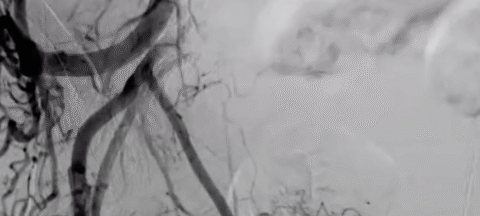

The multicenter PARTEM trial compared PAE to combined medical therapy (alpha-blocker + 5-alpha reductase inhibitor) in men with drug-resistant bothersome LUTS related to BPH >50ml.